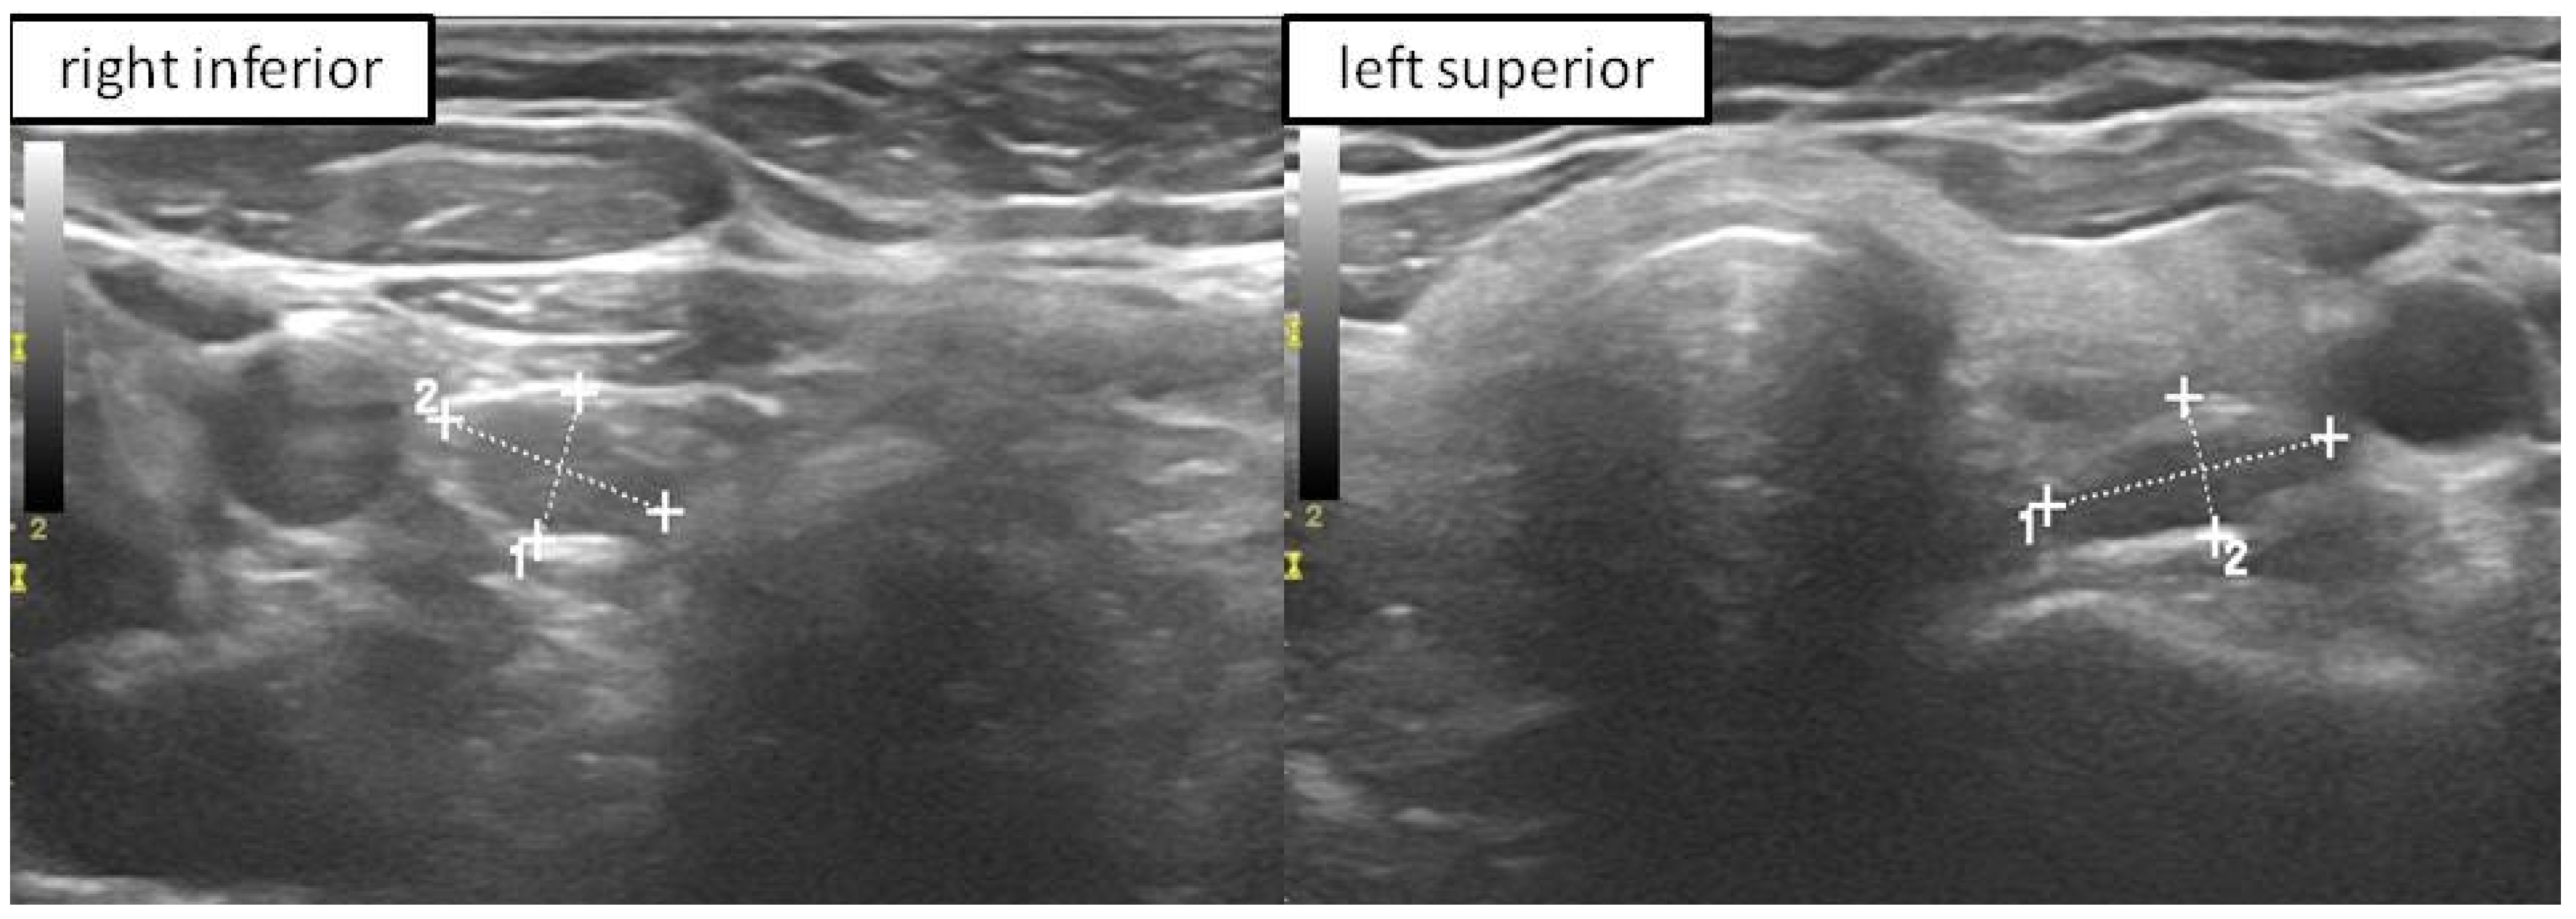

2.4. P-FNAB Procedure

- Visualization of the tip of the needle in PG according to authors’ own scale, QuOBo (Quality of Biopsy; see below for details);

2.7. Parathyroid Quality of Biopsy Scale (QuOBo)

| 2 | needle tip visible inside the parathyroid close to its borders |

| 3 | needle tip clearly visible in the middle of the parathyroid |